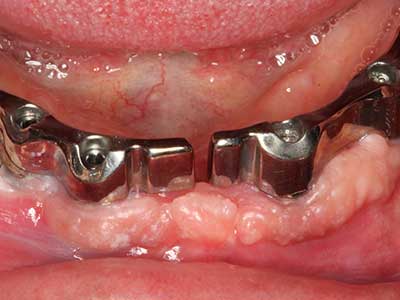

Bei der Knochenblockentnahme zeigen sich weitere Vorteile für die Piezochirurgie: Neben der bereits beschriebenen hohen Präzision bei der Osteotomie stellt sich gerade die Verwendung der dünnen Sägespitzen als besonders materialschonend heraus. Bei der Verwendung insbesondere von Lindemannfräsen sind mit deutlich höheren Entnahmeverlusten durch die dickere Instrumentenspitze zu rechnen (Lakshmiganthan, Gokulanathan et al. 2012). Die insbesondere bei retromolar entnommenen Blocktransplantaten notwendige basale Abtrennung wird durch speziell hierfür vorgesehene rechtwinklige Sägen erleichtert, so dass die Piezochirurgie als präzises, übersichtliches und sicheres Verfahren zur retromolaren Knochenblockgewinnung angesehen wird (Happe 2007) (Abb. 1-12).

Indikation: Bone Splitting